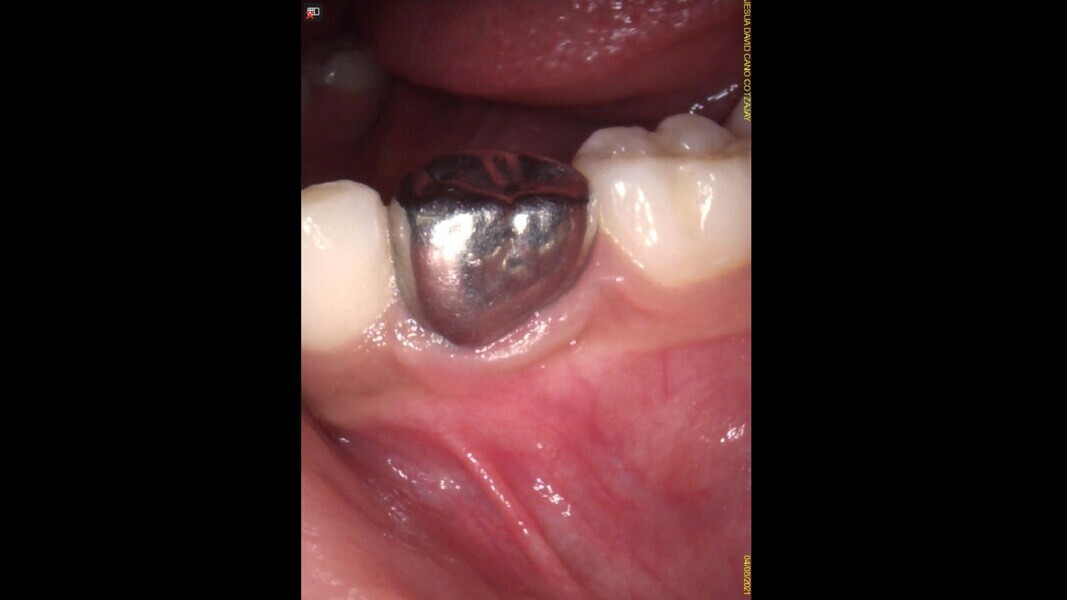

Case 4 (Figs. 14–18)

This male patient was 4 years and 6 months old and presented with constant and spontaneous pain of the mandibular left first primary molar that had lasted for several days but no facial oedema or buccal gingival swelling. Deep decay was observed but no mobility or deep probing depths. On the radiograph, the carious lesion could be seen to be compromising the pulp chamber and initial bone damage was observed in the septal area. Pulpectomy was the treatment of choice. In the removal of the carious lesion, the pulp was exposed and no bleeding was observed. Pulp necrosis was diagnosed. Two mesial and two distal canals were located, and the tooth was obturated. At a second appointment, the tooth was asymptomatic and was restored with a stainless-steel crown. At the 30-month control, the tooth presented no symptoms and a normal eruptive process was observed on the radiograph.